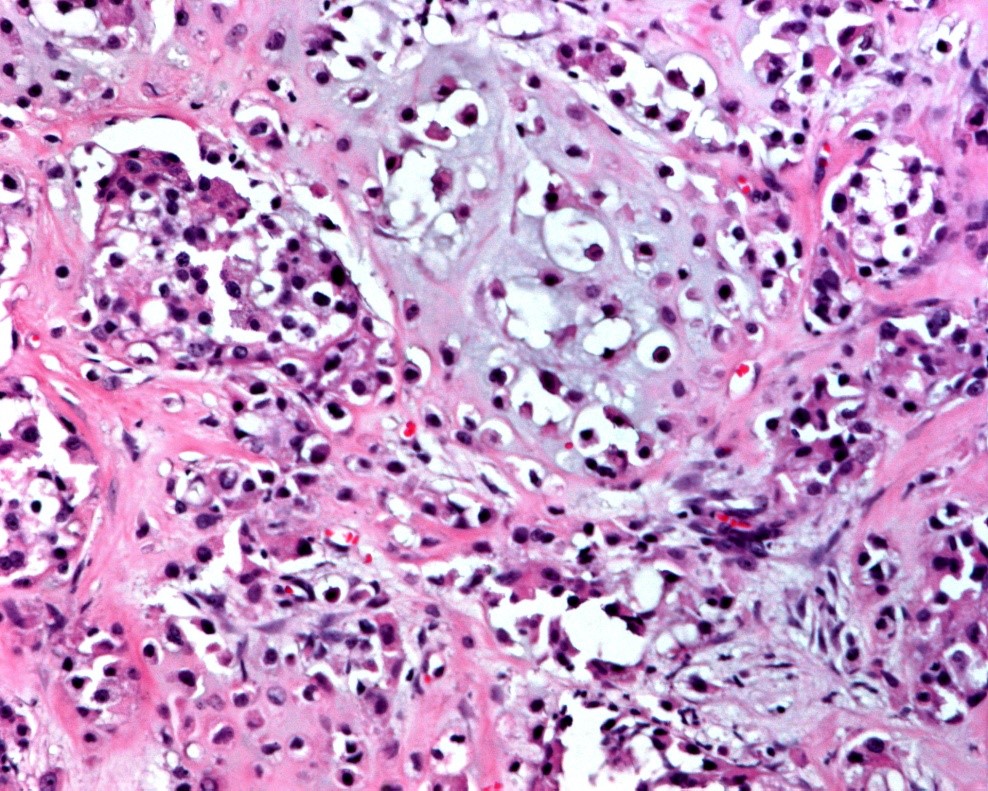

Cortes histológicos de nódulos en axila:

Carcinoma metaplásico productor de matriz o de tipo mixto, con respuesta categoría I de RCB o Miller y Payne 3.